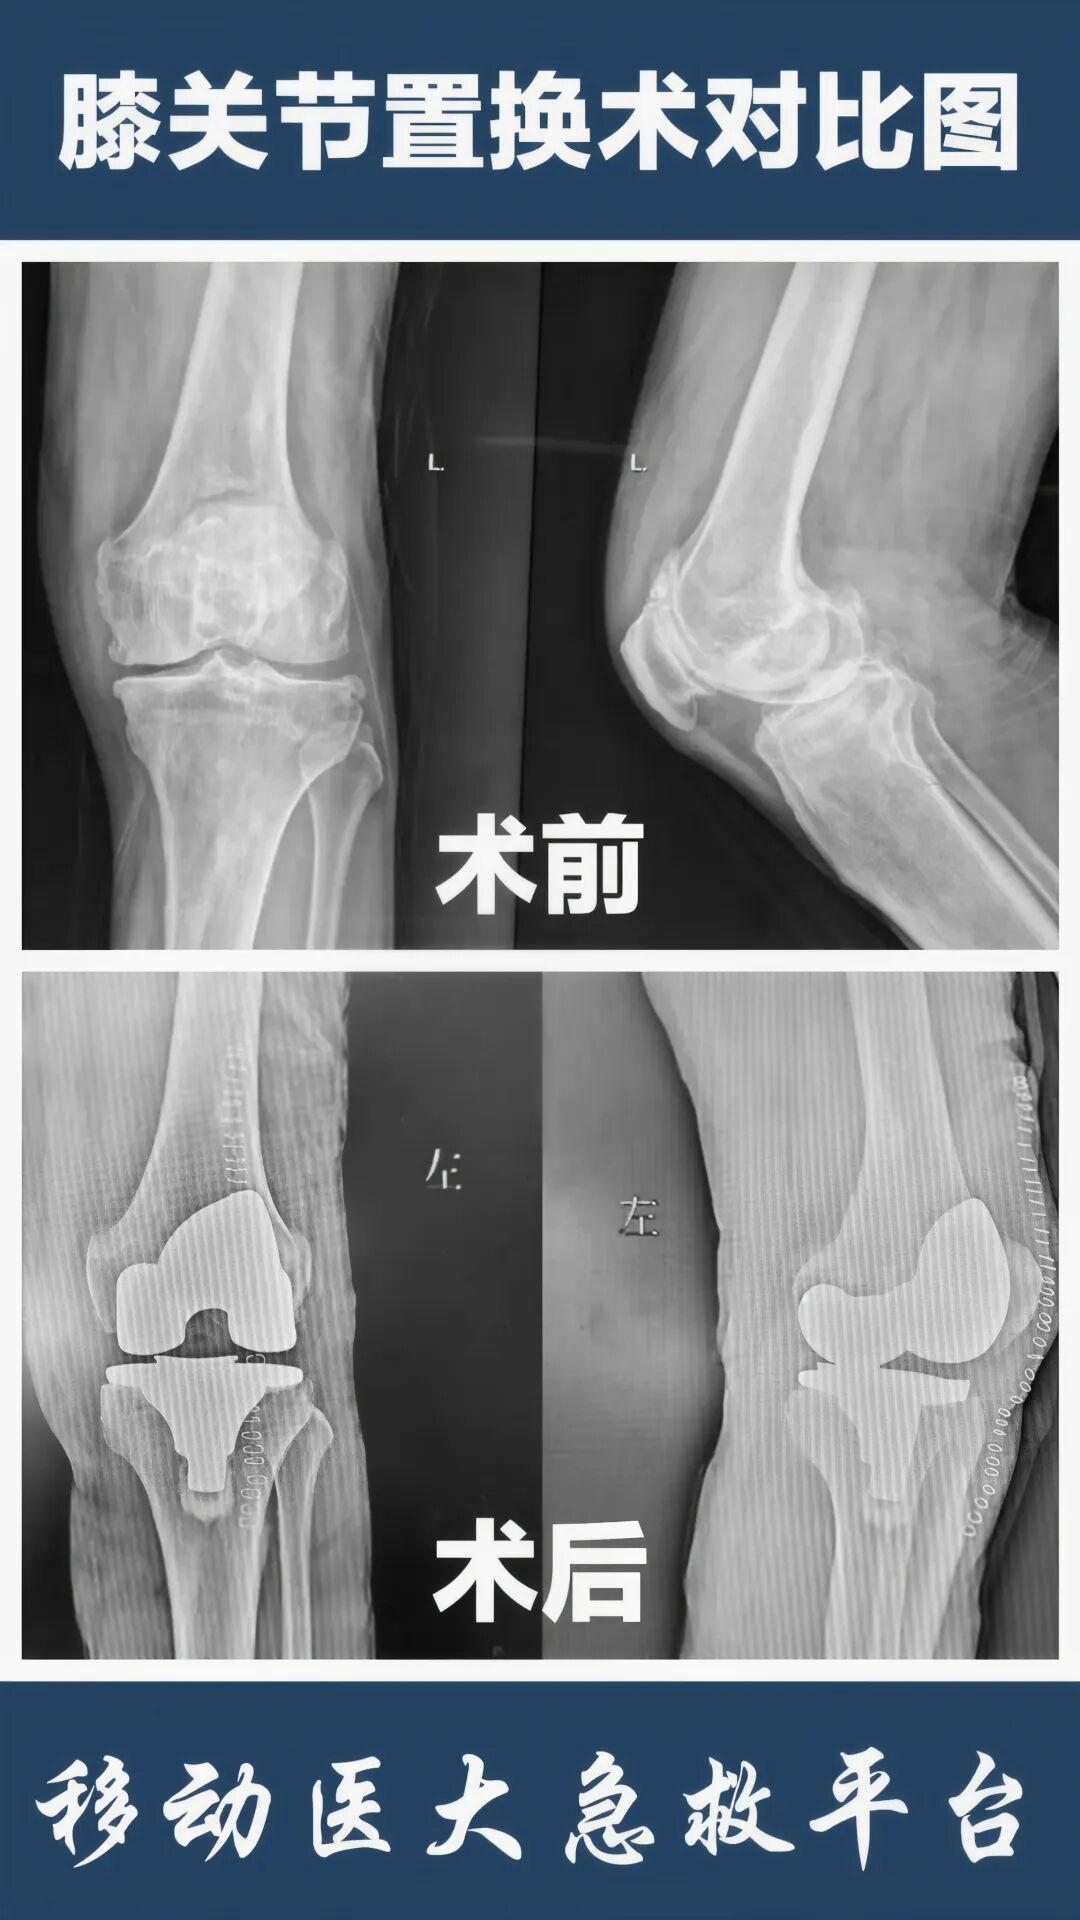

很多患者误以为膝关节置换术就是“换膝盖”,其实这种认识是不正确的。

这项手术的专业名称叫"全膝关节表面置换术",只置换磨损的关节面,就像给牙齿戴牙冠。手术会选择保留关节内外侧韧带,有些还可以保留后交叉韧带,手术出血量非常小。